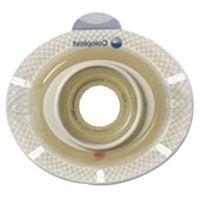

Odor Barrier.Rustle-free pouch.Color Transparent Drain Type Drainable Flange Size 2-3/4 Inch Flange Length 9 Inch Length Material Vinyl Panel No Panel Sterility NonSterile

Hollister CenterPointLock Two-Piece Urostomy Pouch 2-3/4" Flange (Box of 10 Each)

Odor Barrier.Rustle-free pouch.Color Transparent Drain Type Drainable Flange Size 2-3/4 Inch Flange Length 9 Inch Length Material Vinyl Panel No Panel Sterility NonSterile